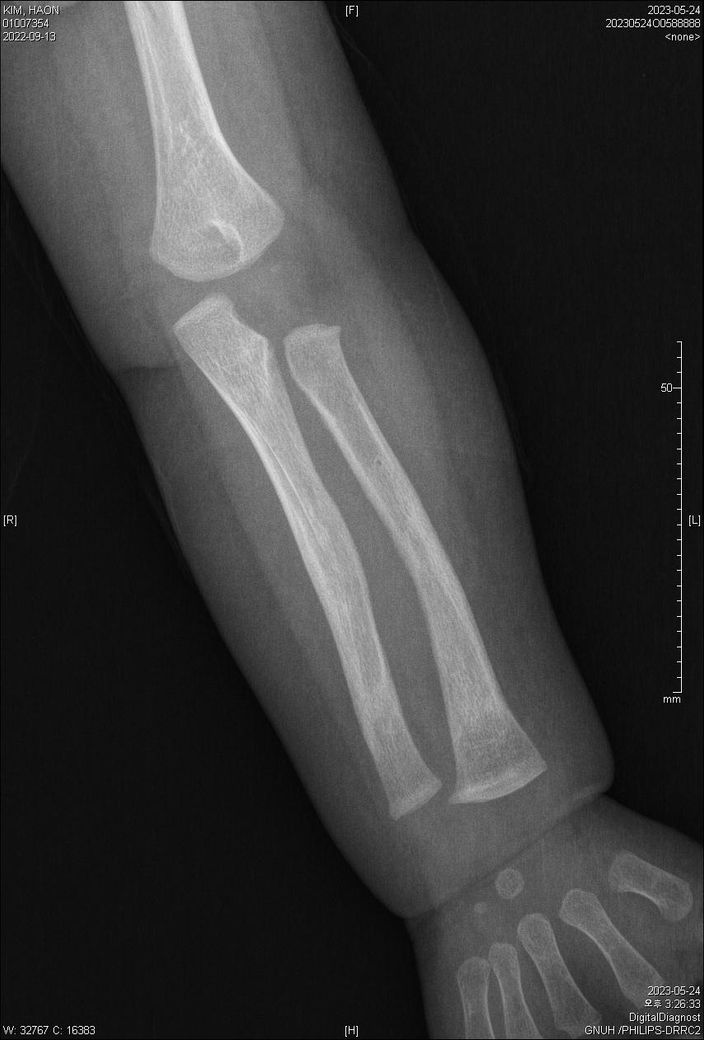

5월 24일 및 7월 11일 X-ray 상의 골절 치유 질의

첨부된 파일에 기재된 사실과 같이 23년 5월 24일 촬영된 양팔 X선 2장과

23년 7월 11일 촬영된 양팔 X선 2장입니다.

양팔이 골절이 되었었는데요,

3) 5월 24일 X선에 비해 7월 11일 X선은 또한 어떤 치료단계인지 문의드리고자 합니다.

4) 종합하자면 3월 초~ 중순에 골절이 일어났다고 보는게 타당한지?

• 2번 째 사진